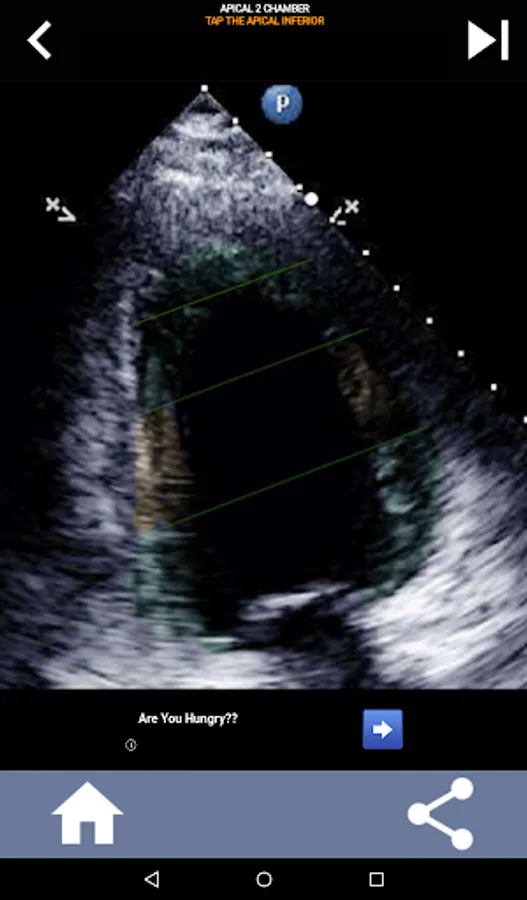

This app will test your knowlegde using actual echo images, which I often find to be the best teaching method.